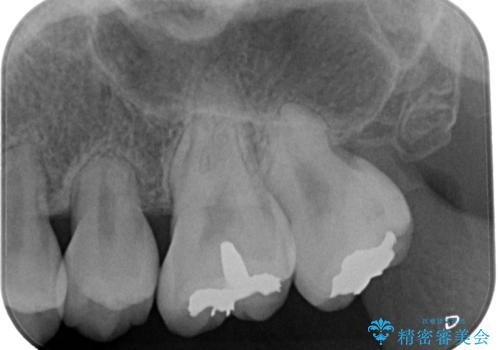

セラミッククラウンの適合はレントゲン写真からも分かる通り、境界がぴったりと合った、高適合のものとなりました。